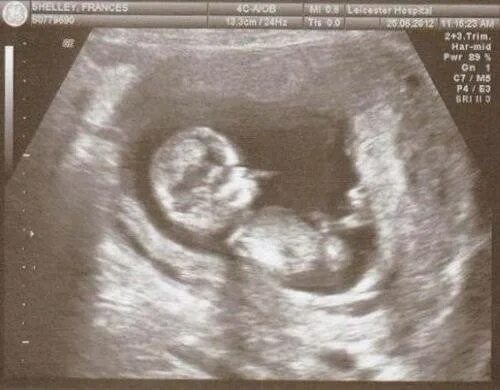

Как выглядит ребенок в 18 недель